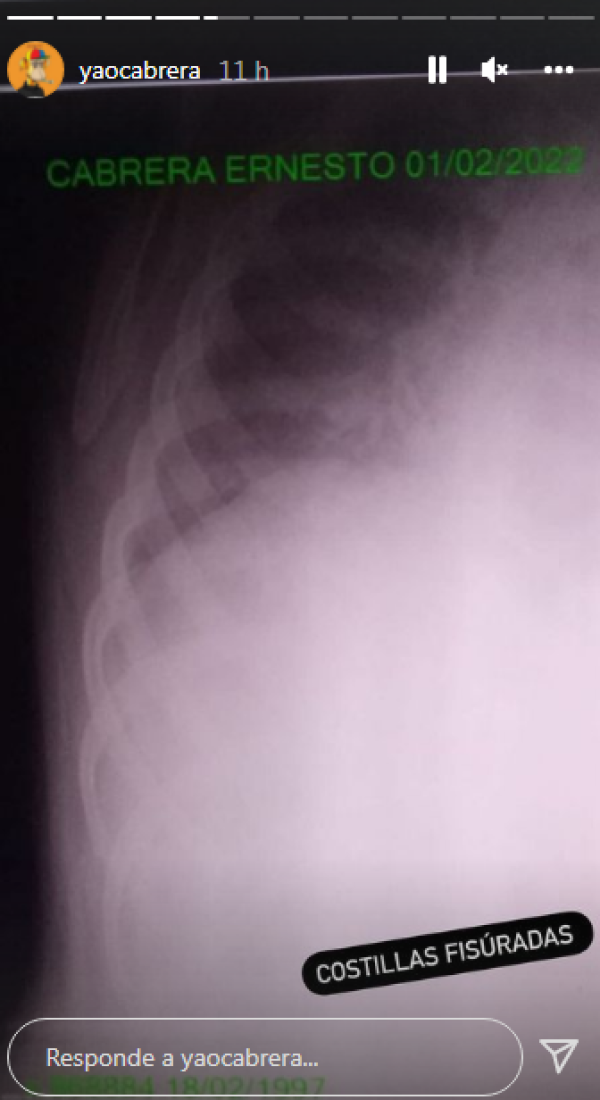

En las últimas horas se confirmó que finalmente, tras las consecuencias del accidente de Yao Cabrera, se suspendió la pelea entre el youtuber el Chino Maidana hasta nuevo aviso.

El propio Yao compartió en su cuenta de Instagram una serie de imágenes que dejan en claro que su caída fue real: